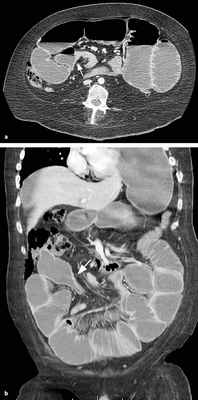

КТ визуализация при простой форме

Хирургическая классификация тонкокишечной непроходимости также является основой классификации, используемой в радиологии. Раличают три формы:

- простая/компенсированная форма

-Расширенные петли тонкой кишки проксимальнее транзиторной зоны (зоны обструкции).

-Под транзиторной зоной надо понимать зонy кишки с очевидной разностью в диаметре просвета между расширенным проксимальным сегментом и местом сужения/обструкции. Визуализация этой зоны зависит от причины и механизма обструкции, а также от проекции расположения петли (аксиально, фронтально и т.д.). К сожалению, обнаружение этой зоны не всегда представляется возможным. При спаечном механизме или воспалении многими хорошо описан признак "птичьего клюва". При обструкции в результате алиментарного болюса транзиторная зона будет выглядеть как гетерогенное образование в просвете кишки без признаков контрастного усиления.

-Спавшиеся петли кишечника дистальнее уровня обструкции.

-Смешанный характер стаза содержимого кишечника в расширенных петлях. Некоторыми авторами описан "фекалоидный" тип стаза, описанный в литературе как "каловое содержимое тонкой кишки", в английской литературе-“small-bowel faeces sign”. Патогенез данного признака включает в себя много факторов:

замедление пассажа содержимого, нарушения механизмов абсорбции и секреции в тонкой кишке, рефлюкс из толстой кишки из-за недостаточности илео-цекального клапана, постановка желудочного зонда. Необходимо помнить, что этот признак неспецифичен при тонкокишечной непроходимости, его также можно определить на УЗИ и обзорной рентгенограмме брюшной полости.

-Нормальные неутолщённые стенки кишечника с гомогенным одинаковым контрастным усилением.

-В тощей кишке рисунок ворсинок слизистой (valvulae conniventes) тонкий, и он одинаково выглядят на всём протяжении.

-Отсутствие патологических изменений толстой кишки, толстая кишка как правило спавшаяся или содержит небольшое количество калового содержимого, распределённого по всему просвету.

-Отсутствие воспалительных изменений в брыжейке и внутрибрюшинном жире.

-Нормальная васкуляризация сосудов брыжейки.

-Отсутствие свободной жидкости в брюшной полости.

Различные КТ сканы при простой форме обструкции, cxематично изображены транзиторные зоны и спайки, которые как "хомут" или "удавка" как-бы душат петлю кишки.

Значение реконструкций в разных проекциях для определения уровня обструкции.